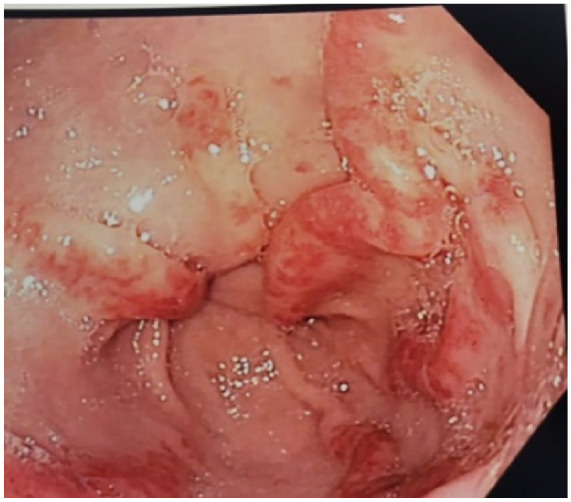

系统性硬化症(SSc)是一种罕见的自身免疫性疾病,导致进行性纤维化和血管功能障碍,经常影响胃肠道,约90%的患者出现胃肠道并发症,严重表现为胃胃窦血管扩张和直肠毛细血管扩张,导致慢性出血和缺铁性贫血。这篇综述和病例报告探讨了胃肠道参与SSc的病理生理,强调纤维化、微血管损伤和运动障碍。它还强调了治疗选择,包括氩等离子凝固等内窥镜干预和药物治疗。

Systemic sclerosis (SSc) is a rare autoimmune disorder that leads to progressive fibrosis and vascular dysfunction, frequently affecting the gastrointestinal tract with around 90% of patients experiencing gastrointestinal complications, with severe manifestations such as gastric antral vascular ectasia and rectal telangiectasia which lead to chronic bleeding and iron-deficiency anemia. This review and case report explore the pathophysiology of GI involvement in SSc, emphasizing fibrosis, microvascular damage, and dysmotility. It also highlights treatment options, including endoscopic interventions like argon plasma coagulation and pharmacological therapies.